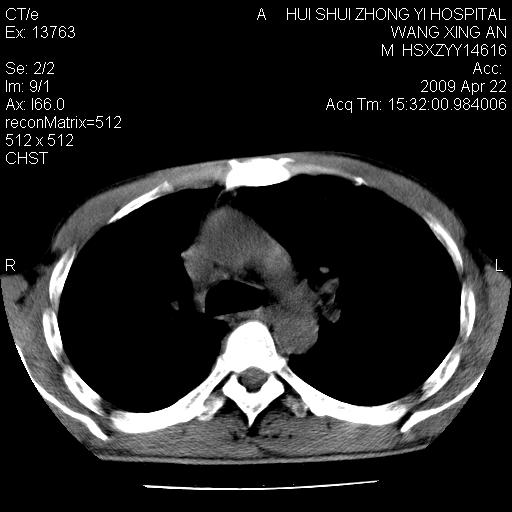

标题: CT19534:患者男、46岁咳嗽、胸痛半月。 [打印本页]

标题: CT19534:患者男、46岁咳嗽、胸痛半月。

1、右下肺中央型肺癌并右肺转移,右肺中下叶不张。(右肺有结节影)。胸骨转移

右侧中心性肺癌并下叶肺不张,双肺及纵隔淋巴结转移,右侧胸腔积液

1)右肺中间段支气管癌并右肺下叶肺不张。2)右肺上叶、两肺下叶背段感染性病变。3)右侧少量胸腔积液。